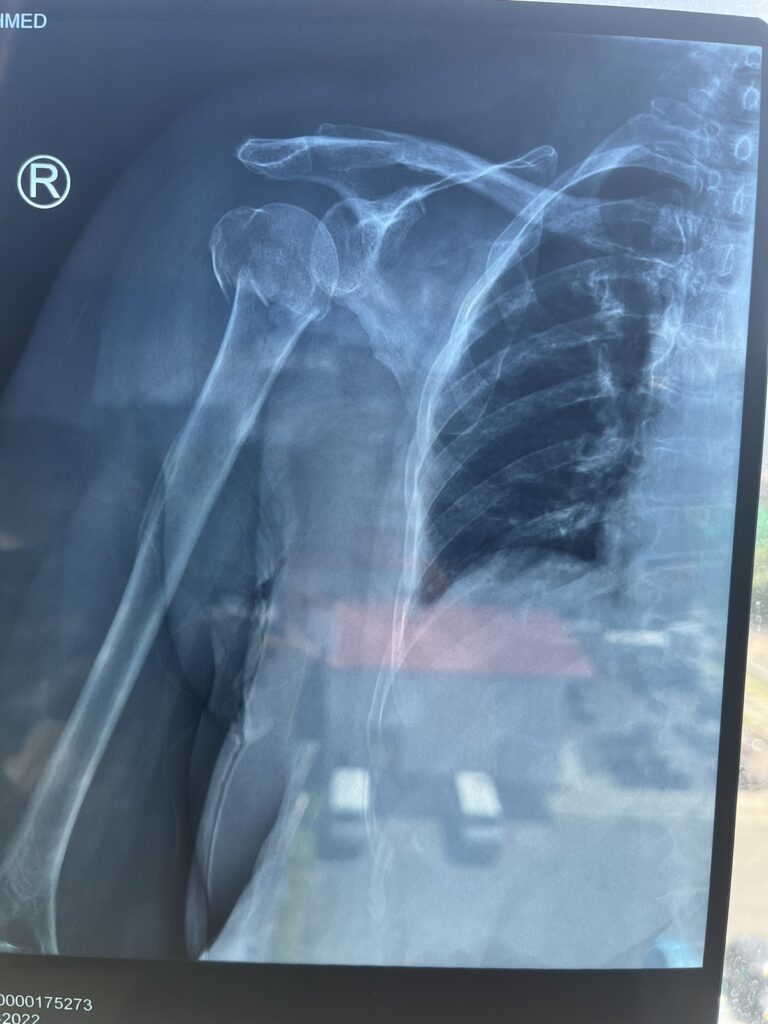

“މަންމަ ބުނީ ބަސް ފަހަތުން އައިސް ޖެހުނީ މަންމަގެ ކޮނޑުގައި ކަމަށް. ދެން ކޮންމެ ގޮތެއްވިއަސް އެވަރުގެ ބަހަކުން ޖެހޭއިރު ސައިކަލުން ވެސް ވެއްޓޭނެ ދޯ. އަހަރުމެން ވެއްޓުނު ހިސާބަށްވުރެ 100 ފޫޓެއްހާ ދުރަށް ދިޔަ ފަހުން ބަސް މަޑުކުރީ. އެ މީހުން ބުނި އެހާ ގިނަ މީހުން ގޮވައިގެން ދަތުރު ކުރާއިރު ކުއްލިއަކަށް މަޑުނުކުރެވޭނެއޭ” އާއލާއިން ބުންޏެވެ.